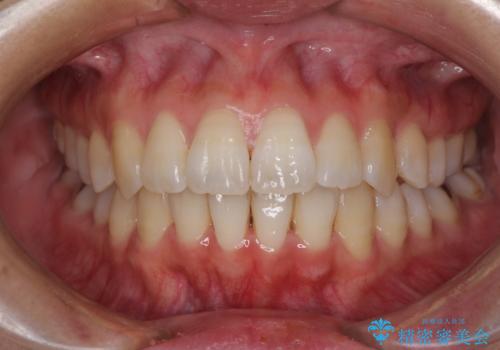

[インビザライン ライト] 短期間(3.5ヶ月)で終わるマウスピース矯正

![[インビザライン ライト] 短期間(3.5ヶ月)で終わるマウスピース矯正の症例 治療後](https://seimitsushinbi.jp/wp/wp-content/uploads/2020/02/2f36cdf472a802b537022ae239b8cb6b-500x350.jpg?v=1580813669)